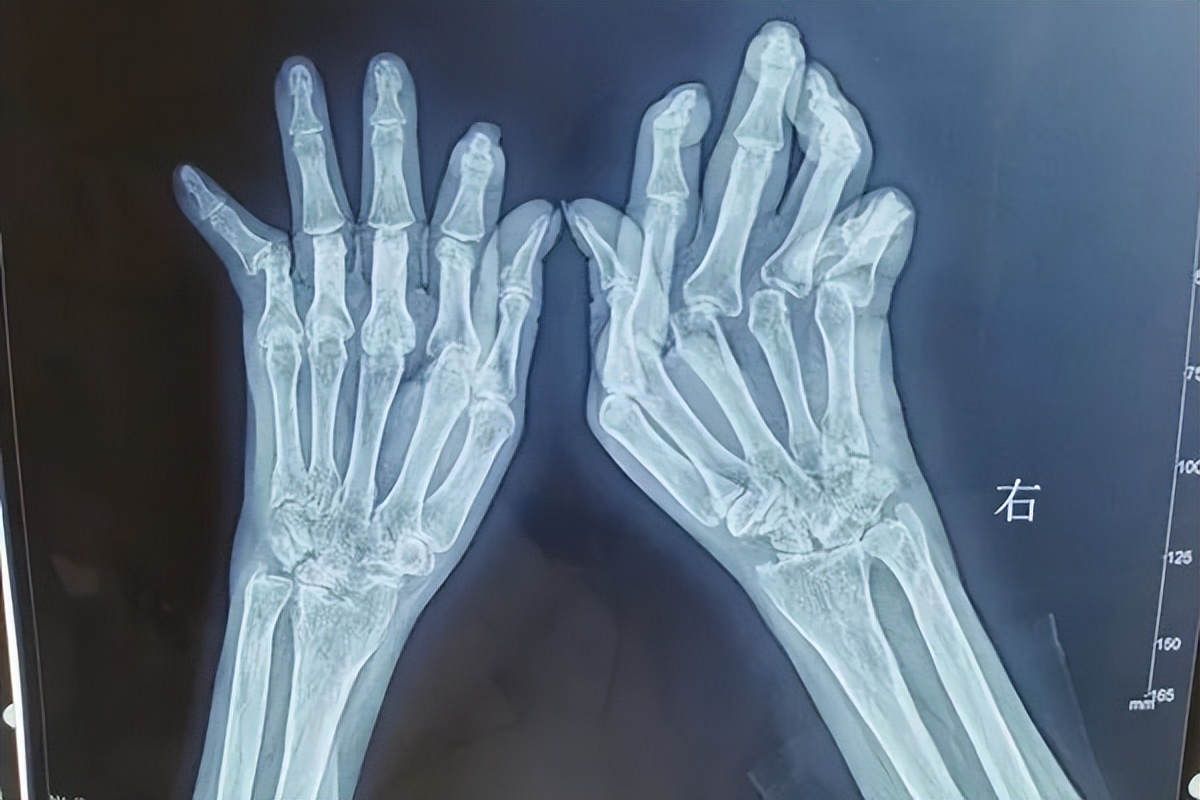

类风湿治疗的关键在于先检查免疫问题以及关节腔内部骨破坏的情况。可通过专科 肌骨超声、微循环、免疫代谢检查 ,明确炎性因子分布、软组织滑膜骨质破坏程度、血液循环情况、免疫失衡原因,才能精准祛炎和修复受损骨质以及解决怕风怕冷疼痛和变形的问题。

类风湿患者活动受限,关节变形是因为软骨受损、骨间隙变窄黏连融合等因素导致的,通过 关节PRP技术 介入注射治疗,将损坏的软骨修复成原有正常的组织结构,加快软骨修复和促进骨细胞再生、解决类风湿“关节致残·根在骨细胞”的问题,从而达到恢复关节功能和保护关节的作用。